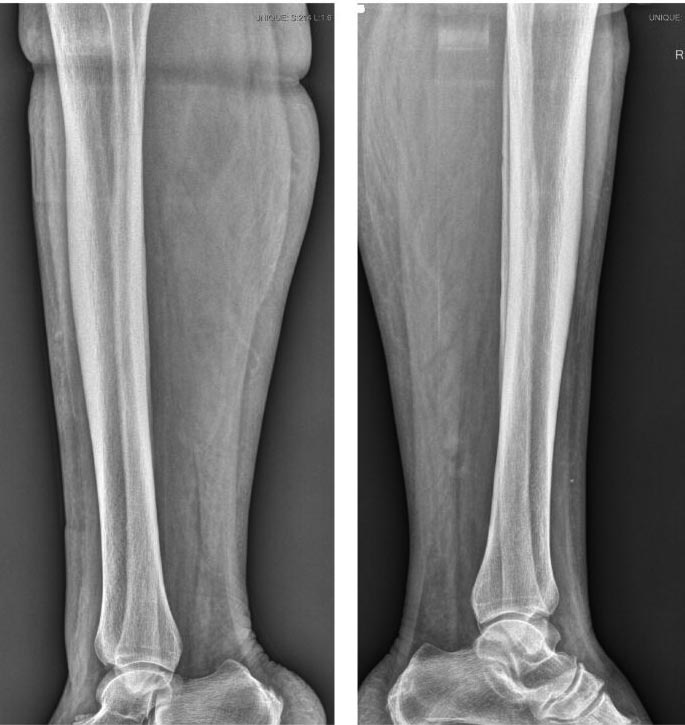

Боковой снимок